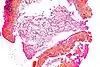

| Tinción hematoxilina-eosina | Bicomponente Anfifílica |

|

Tinción histológica general | ![]() |